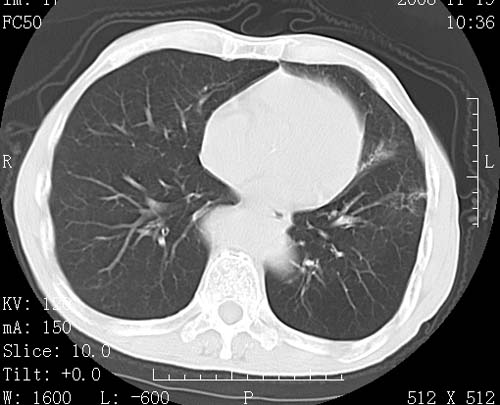

术前查体,双肺部结节是转移?结核?请点评

1)符合食管癌表现。2)两肺及纵隔淋巴结多发性转移瘤。3)左肺上叶舌段及两肺下叶炎症感染。

食管癌伴双肺转移,评述:肺部毛细血管网丰富,全身血液均快速流经肺部,癌细胞容易过滤定植,形成转移瘤,影象特点为以毛细血管末梢为中心的结节灶,边缘光滑锐利,少见有中心空洞着,不同来源的转移瘤可有各自特点,如甲状腺癌为双肺弥漫性微结节,本例有原发灶,双肺影象灶典型,左肺舌段条带状网格样伴胸膜天幕征,可视为癌性淋巴管炎。